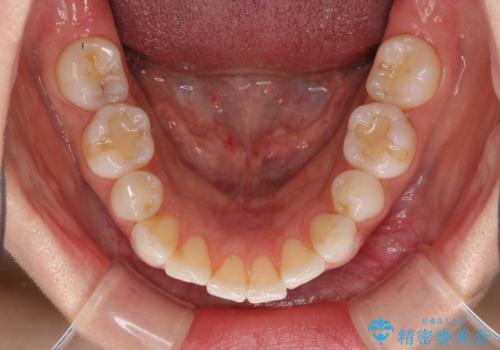

矯正治療の後戻り インビザラインによる再矯正治療

- 以前ワイヤー装置にて行った抜歯矯正の後戻りを気にして来院された患者様です。

前歯のデコボコにより、やや口元が突出した印象となっていたため、口元も引っ込めることとしました。

上下顎前歯に積極的にIPR(歯と歯の間を削る)を行い、インビザラインを用いて治療していくこととしました。

デコボコが解消されるのはもちろんのこと、突出感のあった前歯を引っ込めることができ、患者様には大変満足していただきました。